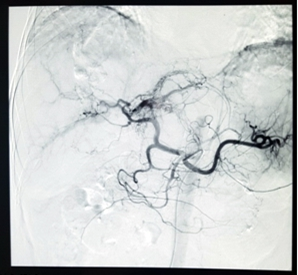

Hình 2. Ảnh các động mạch gan quan sát được thông qua ĐQCT

Các bác sỹ ĐQCT sẽ sử dụng cắt lớp vi tính, cộng hưởng từ, hoặc siêu âm để đánh giá bộ phận tổn thương cần điều trị.

Tiếp theo, họ đặt một dụng cụ vào cơ thể thông qua một vết cắt nhỏ. Các dụng cụ này có thể là một chiếc kim, một ống catheter, hoặc một đoạn dây đặc biệt. Bác sĩ quan sát vị trí đặt dụng cụ vào cơ thể thông qua màn hình để đưa dụng cụ tới vị trí cần điều trị.